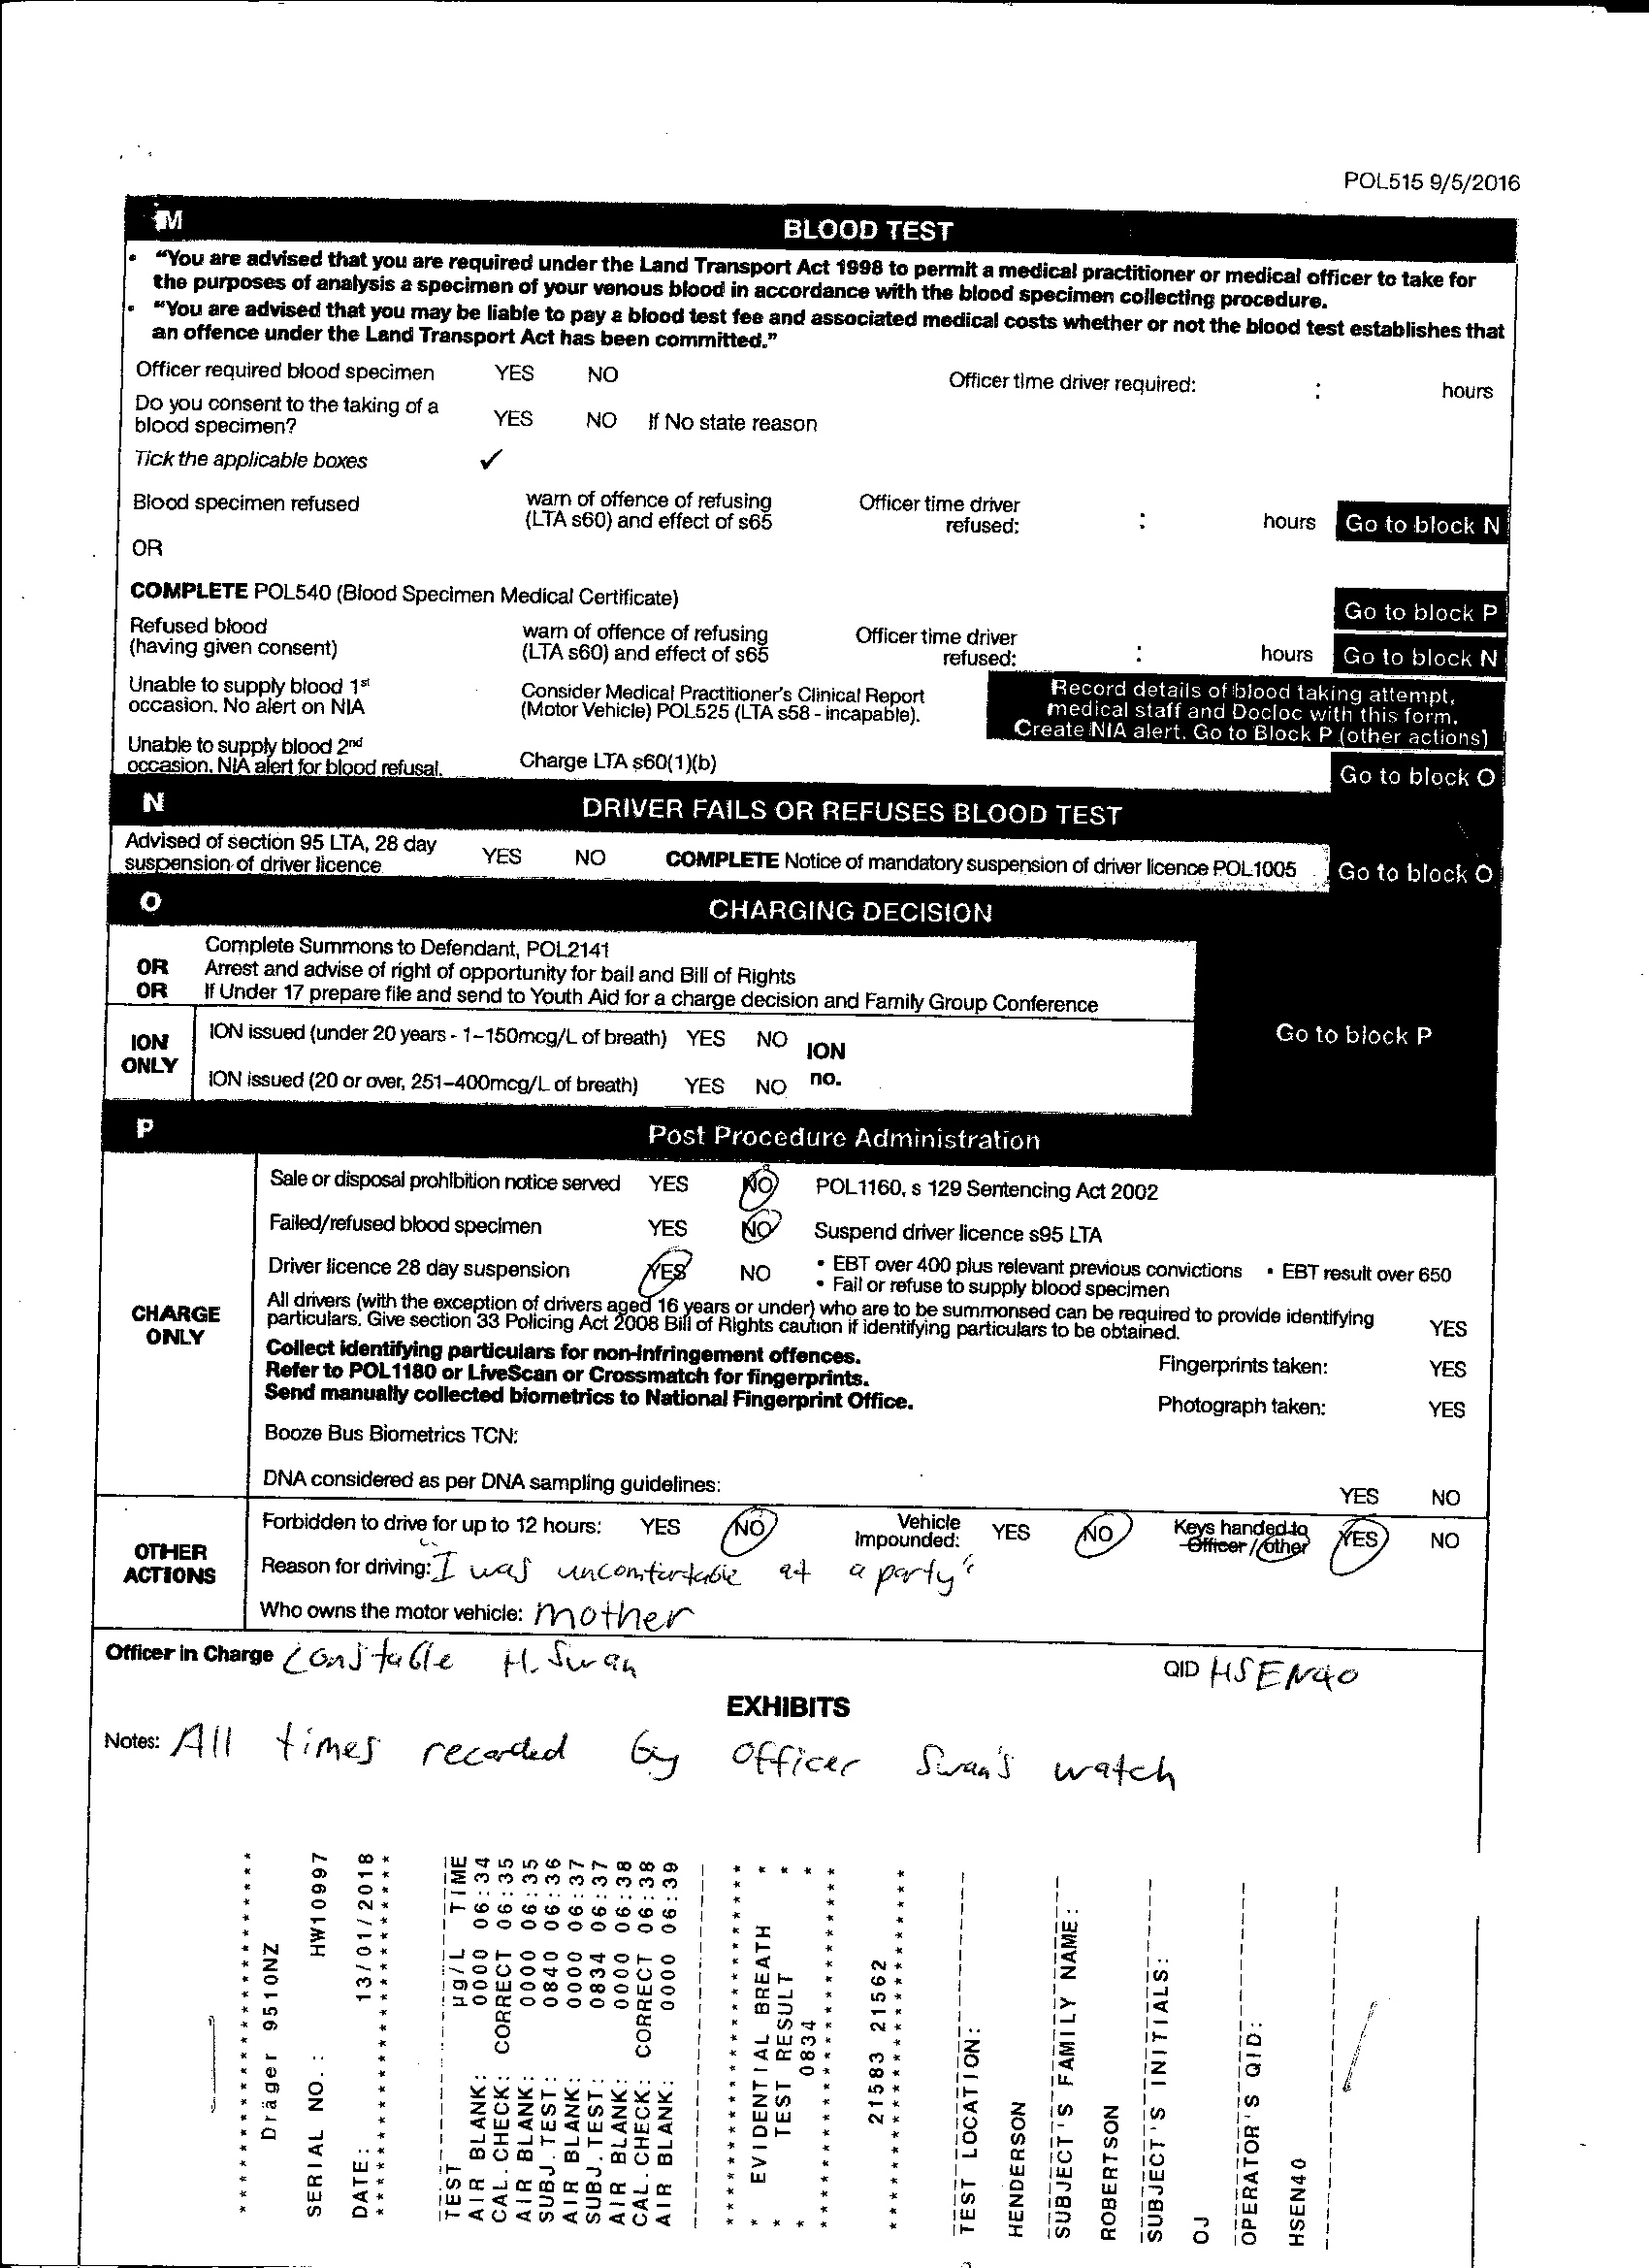

Medical Wrap, Moon Boot, House Paint, Car Mats, Wetsuit, Projection, Casts, Video Work Forensics investigates trauma both physical and mental and how the two might interact through objectivity.